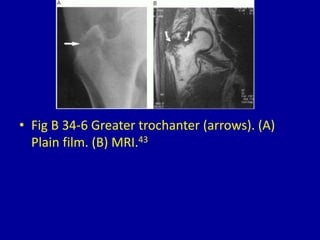

This document provides descriptions and images of avulsion injuries at various anatomical locations in the body. Avulsion injuries refer to the tearing away of a tendon, ligament, or muscle from the bone. The document lists 17 figures showing examples of avulsion injuries at locations such as the ischial tuberosity, anterior superior iliac spine, anterior inferior iliac spine, symphysis pubis, lesser trochanter, greater trochanter, fibular head, tibial eminence, posterior cruciate ligament, tibial tuberosity, inferior pole of the patella, calcaneal tuberosity, anterior and posterior capsule of the ankle joint, greater and lesser tuberosity of the